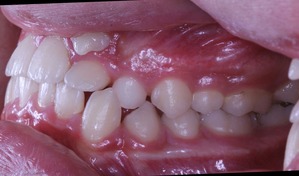

それでは治療開始前の状態です

このように1番目と2番目の歯の間から犬歯3番目の歯が生えてきました。

また乳歯Cが残っているので 歯の順番でいうと

132Cという順番になっております